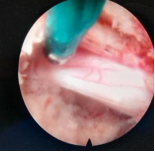

6.显微镜下脊柱椎管内肿瘤切除技术

椎管内肿瘤是指发生在脊髓、脊神经根、脊膜和椎管壁组织的原发性或继发性肿瘤,主要表现为阵发性疼痛及肢体感觉异常。根据肿瘤与脊髓、硬脊膜的位置关系可分为髓内肿瘤、髓外硬脊膜下肿瘤和硬脊膜外肿瘤。椎管内肿瘤是脊柱外科的常见病,可发生于任何年龄,多见于中年人。好看视频下载

常规开展显微镜下颈椎、胸椎、腰椎椎管内肿瘤摘除术,在显微镜的帮助下逐层绕开皮下组织、肌肉、到达椎骨以后只需要开个小口就能进入椎管,找到肿瘤,然后将它一点点地清除。